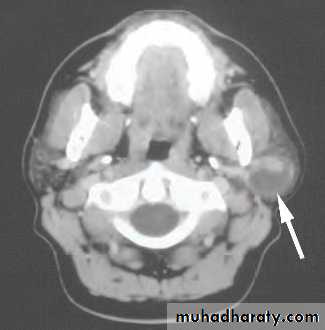

CT&MRI; characteristic Swiss cheese appearance of multiple large cystic lesions.